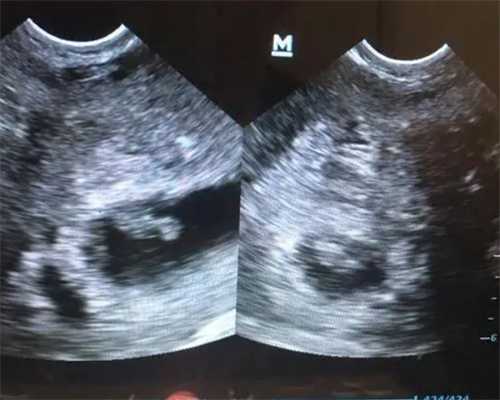

重庆捐卵盲捐多少钱 附重庆试管婴儿医院明细 ‘彩超孕囊怎么看男女’

重庆捐卵盲捐多少钱 附重庆试管婴儿医院明细 ‘彩超孕囊怎么看男女’tips